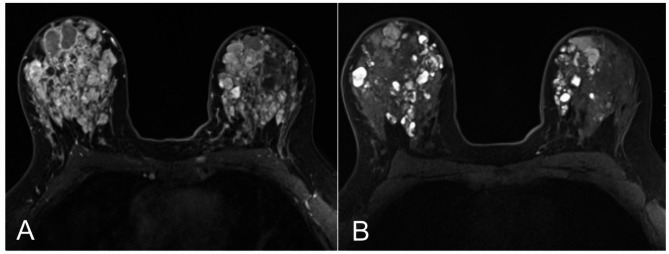

Case presentation: We describe a 26-year-old woman with longstanding bilateral palpable breast masses and spontaneous bloody nipple discharge. Imaging revealed numerous cysts and masses, predominantly in the right breast. Multiple biopsies showed benign papilloma with focal atypical ductal hyperplasia (ADH), while total mastectomy specimens revealed multifocal, poorly differentiated, triple-negative invasive carcinoma. An axillary lymph node contained ectopic breast tissue with associated papillary proliferation. Genetic testing identified a pathogenic germline PTEN variant (c.209 + 4_209 + 7delAGTA), confirming PTEN hamartoma tumor syndrome (PHTS).